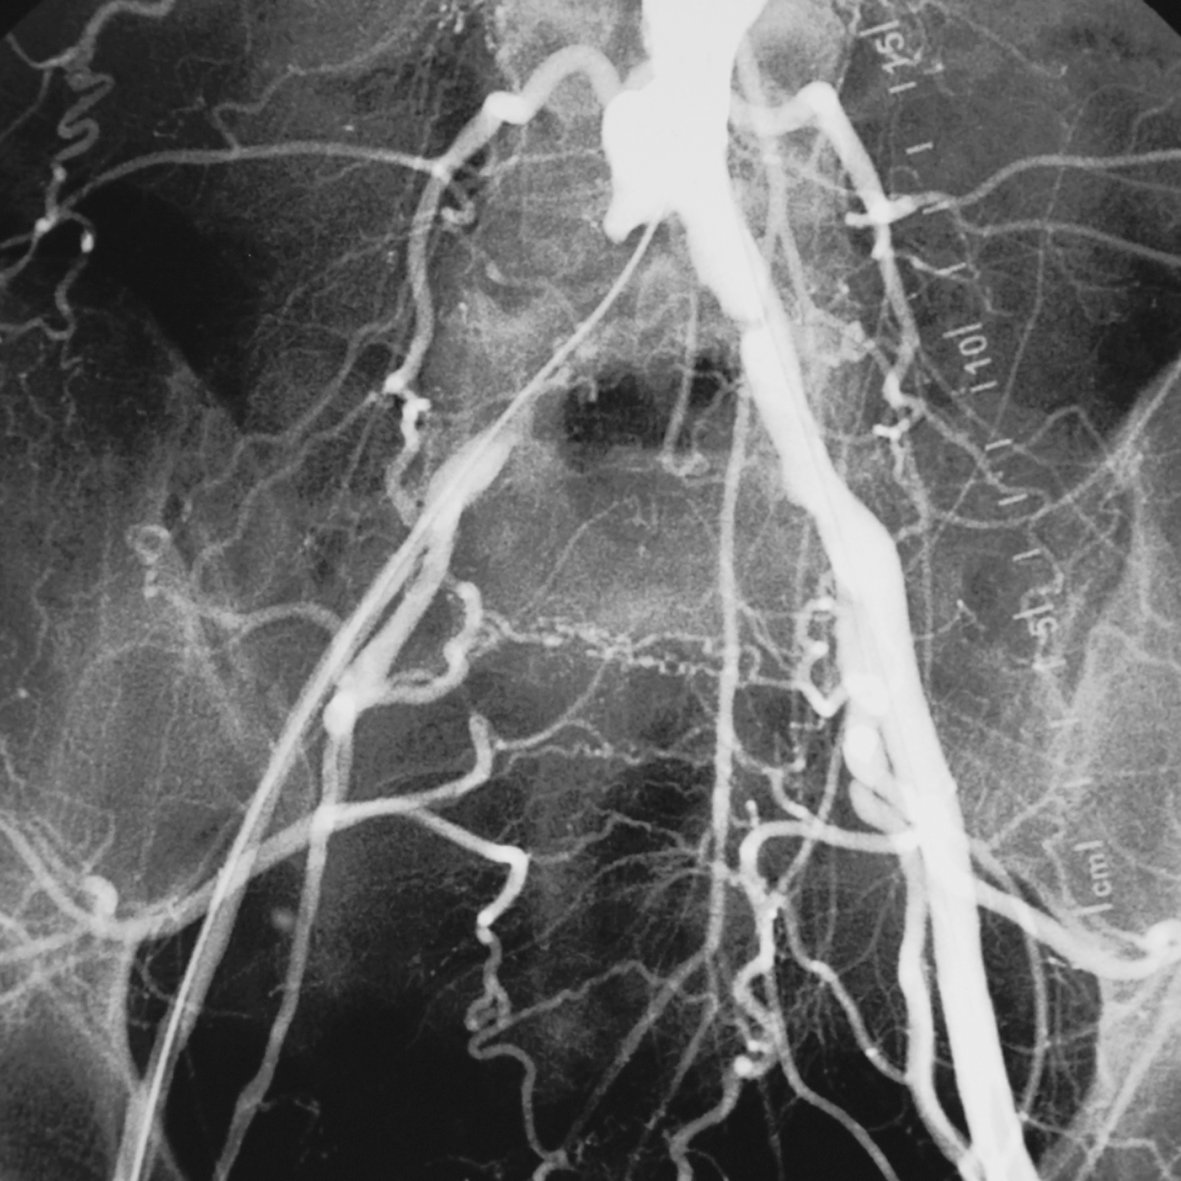

Digitale Substraktions Angiographie (DSA)

Auch die DSA dient der Darstellung der Gefäße. Dazu wird ebenfalls Kontrastmittel verwendet. Durch eine spezielle Technik sind die Gefäße mit der DSA besonders fein darstellbar. Dies ist beispielsweise bei der Diagnostik der Schaufensterkrankheit, auch periphere arterielle Verschlusskrankheit (pAVK) genannt, wichtig. Dabei sind feinste Gefäße in den Beinen verengt oder verschlossen.

Um zu verhindern, dass Zellen im schlecht durchbluteten Bereich untergehen, ist die DSA eine sichere Möglichkeit die Schaufensterkrankheit festzustellen und einer Behandlung zuzuführen.